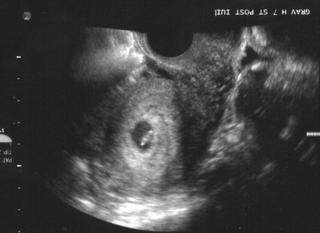

Ahojte, tak zajtra koncim s clostylom, v pondelok ma caka folikulometria , inak neviete aka je idealna velkost folikulov?